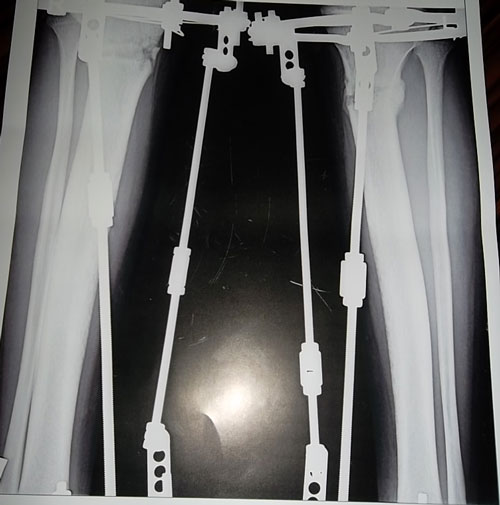

ИСХОДНИК

Дата операции 27.09.2012г.

SAM_3983.JPG